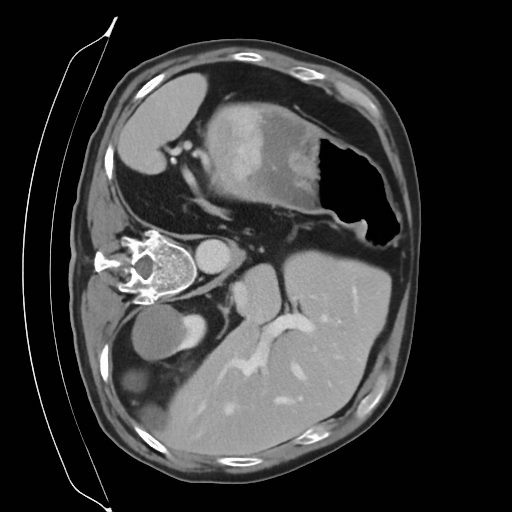

Sampling results

Original

Perturbed

Samples

Sampled